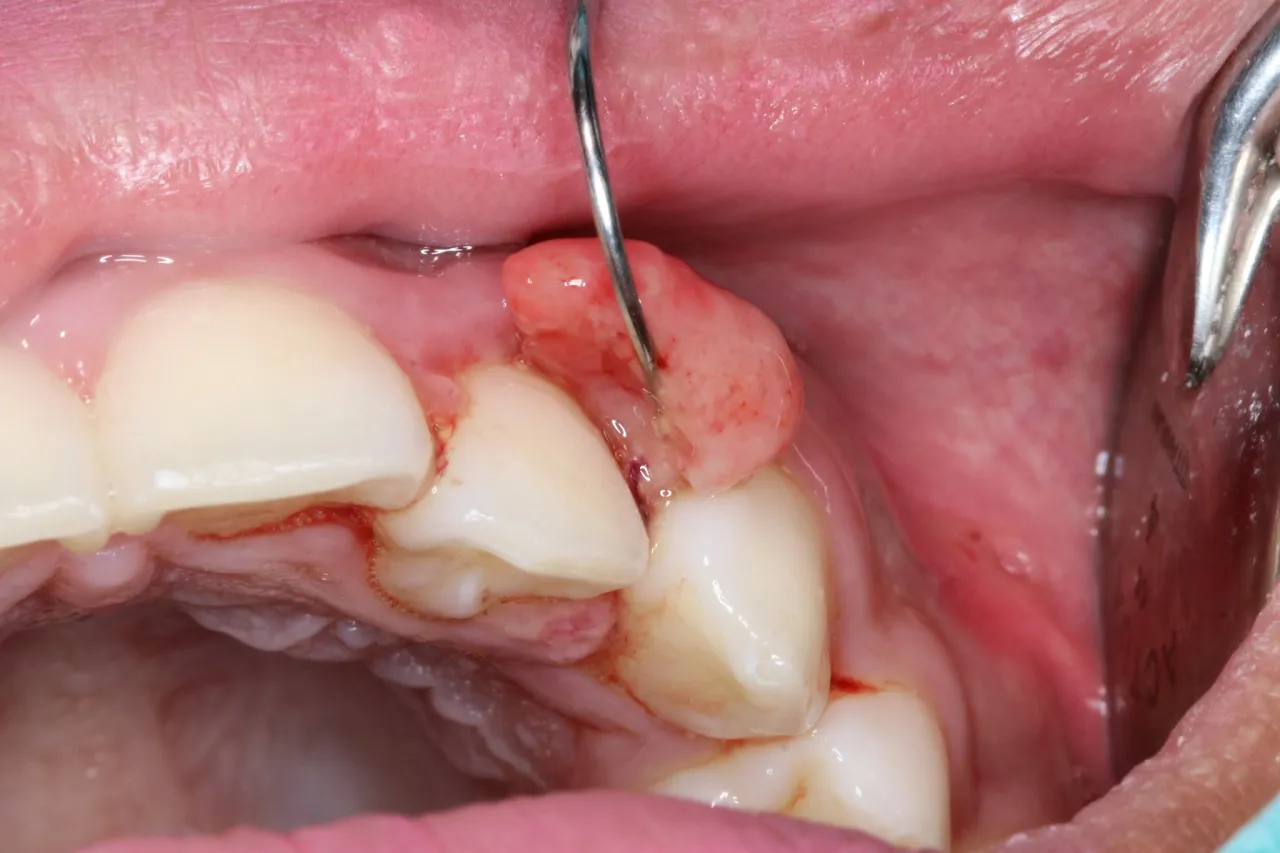

Zgrubienia i guzki w jamie ustnej - co oznaczają?

Zgrubienia i guzki w jamie ustnej mogą być ważnym sygnałem, że coś jest nie tak z naszym zdrowiem. Ich obecność może sugerować różne stany, w tym nowotwór jamy ustnej. Zgrubienia mogą mieć różne kształty, rozmiary i tekstury. Często są bezbolesne, co sprawia, że wiele osób nie zwraca na nie uwagi. Jednakże, jeśli zgrubienie nie znika w ciągu kilku tygodni, należy to traktować poważnie.

Warto również zwrócić uwagę na lokalizację guzka. Guzki w obrębie języka, warg czy policzków mogą być bardziej niepokojące niż te na dnie jamy ustnej. Oprócz nowotworów, zgrubienia mogą być wynikiem infekcji, stanów zapalnych lub innych schorzeń. Dlatego kluczowe jest, aby monitorować wszelkie zmiany i konsultować się z lekarzem, jeśli zauważymy coś niepokojącego.